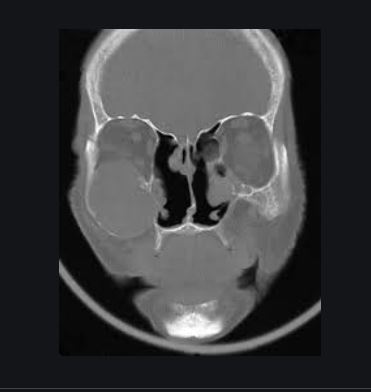

zystische Raumforderung am Hals rechts , axiale Schichtung CT.

V.a Laterale Halszyste